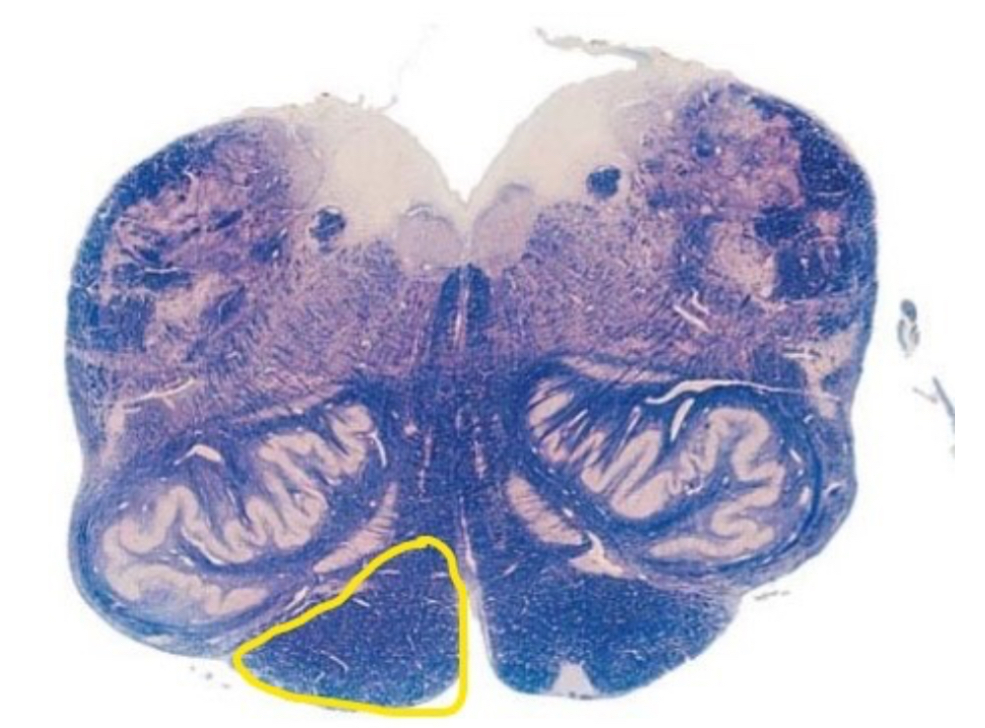

8

Q

The section is through the ________________?

A

caudal pons

9

The yellow line represents?

axons of CN VII